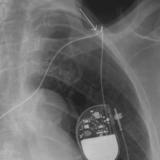

Biventricular ICD

Date: 10/22/2010

Views: 4396